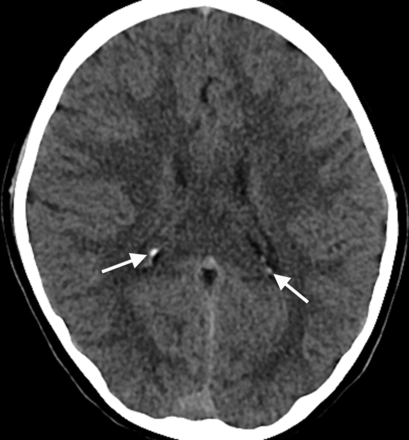

Twelve percent of subjects (n = 58) had choroid plexus calcifications (age range, 0.1–8.8 years; median, 6 years; Fig 3). All choroid plexus calcifications were localized to the lateral ventricular glomus. Most choroid plexus calcifications were punctate and/or few (n = 54). The 4 remaining patients with large and/or numerous choroid plexus calcifications were 8 (n = 3) and 3 (n = 1) years of age. There was a significant association between patients with choroid plexus and pineal calcifications (P = .003).

Axial head CT image from an 8-year-old child obtained for seizure, at the level of the lateral ventricular atria, depicting choroid plexus glomus calcifications (arrows).

We discovered choroid plexus calcifications in 12% of patients in our cohort. In accordance with findings described by Doyle and Anderson,13 we found a significant positive association of choroid plexus and pineal calcifications. Choroid calcifications were visible in patients across all age ranges, from younger than 1 month to 10 years. A variety of clinical scenarios brought these patients to imaging, mainly trauma and headache. In all cases, the choroid plexus glomus was calcified in isolation, either unilaterally or bilaterally. Typically, calcifications were punctate and few. Therefore, choroid plexus calcifications occurring outside the glomus or in excess should be viewed with suspicion for underlying pathology in patients younger than 9 years of age. Minimal choroid plexus calcium deposition is probably physiologic at any age, including early childhood.